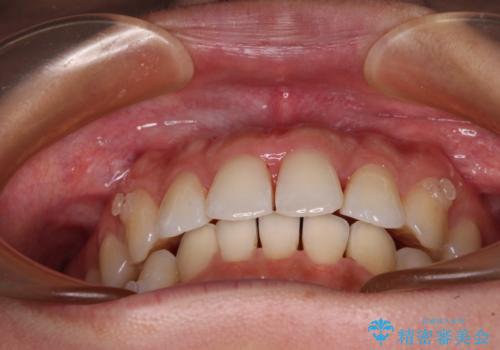

捻れた前歯をインビザラインで整える

- 捻れた前歯が飛び出しており、口が閉じにくいとのことで来院された患者様です。

出っ歯というわけではないものの、前歯の捻転により口唇が押し出されている状態でした。

親知らずを抜去し、歯列全体を後方に移動させつつ、IPR(歯と歯の間を削る)でスペースを獲得し、インビザラインを用いて叢生を解消しながら前歯の突出を改善することとしました。

骨格的に上下正中がずれていたため、奥歯がしっかりと噛み合うか心配でしたが、ずれているなりに、しっかりとした咬み合わせとなりました。